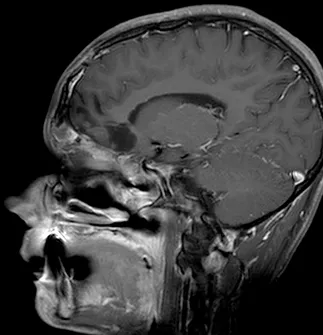

一名15岁、既往健康的男性,因额部头痛加剧、恶心、呕吐和疲劳两周病史就诊。家属注意到在就诊前一个月出现言语失控和非典型行为。他的神经系统检查显示双侧视乳头水肿,无其他局灶性缺损。所有血液检查均正常,血清生殖细胞肿瘤标志物也为阴性。脑和鼻旁窦的计算机断层扫描(CT)和磁共振成像(MRI)扫描显示,右侧有一个5.5 x 4.4 x 5.6厘米的肿块,起源于鼻腔、筛窦和蝶窦。它已侵蚀筛板进入前颅窝。该肿块在CT扫描上未钙化(图1),与脑组织等密度,伴有不均匀的对比增强。该肿块在T1和T2加权MR图像上(图2、3、4)与脑组织等信号,并在钆增强后显示不均匀强化。注意到周围有血管源性脑水肿和占位效应。脊柱MRI未见转移证据。

图3:矢状位T1加权钆增强MRI扫描,显示肿瘤团块从鼻旁窦侵蚀进入前颅窝。

Epstein Barr病毒(EBV)原位杂交为阴性。电子显微镜显示为原始小细胞和较大的上皮细胞的混合物,上皮细胞具有形成良好的长细胞间连接。诊断为SNUC。术后,他的神经系统状况无变化,头痛在术后第十天出院回家前显著减轻。术后两天进行的磁共振成像显示肿瘤大体全切。他接受了辅助分割放疗,包括对肿瘤床和周围边缘进行的30次分割共6000 cGy的照射。同时给予了顺铂化疗。术后十二个月,患者神经系统状况良好,无影像学或临床证据表明肿瘤复发(图7、8)。

图8:矢状位T1加权钆增强MRI扫描,显示鼻旁窦和前颅窝肿瘤的大体全切。注意额叶无占位效应,肿瘤腔内无对比增强。